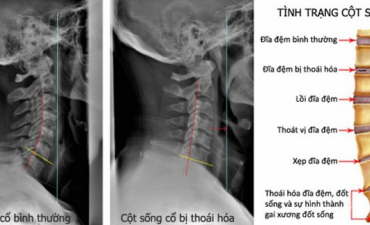

Chữa thoái hóa đốt sống cổ bằng lá lốt là một phương pháp đơn giản nhưng hiệu quả, mang lại nhiều tác dụng tốt cho sức khỏe, đặc biệt là trong việc điều trị các bệnh lý liên quan đến xương khớp.